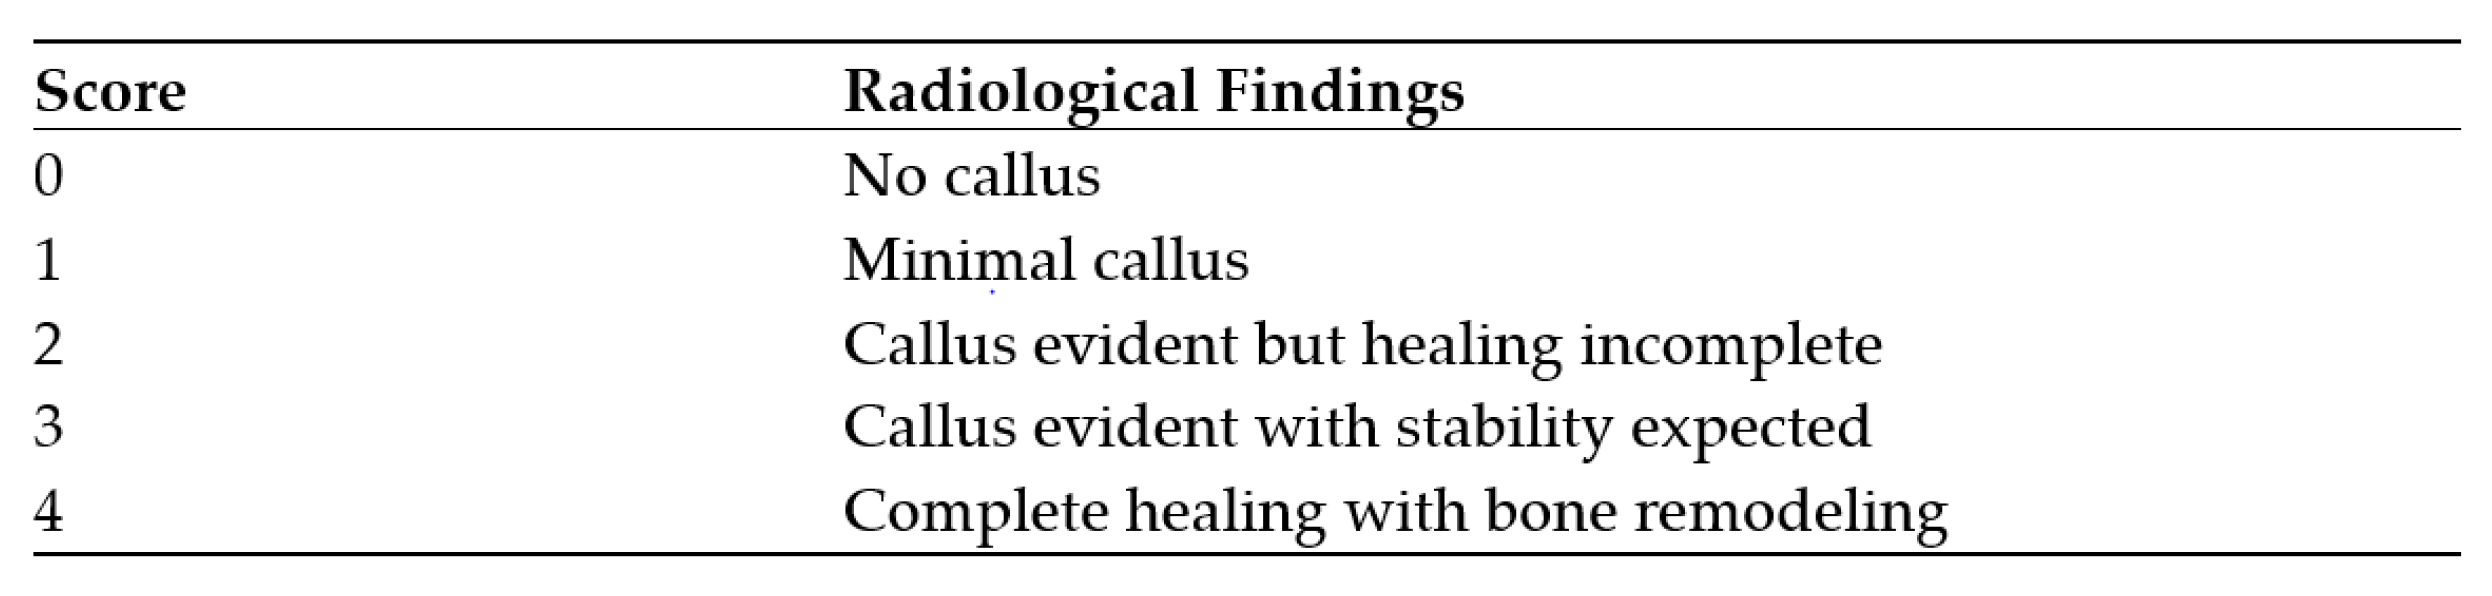

| Lane-Sandhu-score after 1 year | no callus | 3 | 23.1% |

| minimal callus | 1 | 7.7% | |

| callus evident but healing incomplete | 0 | 0.0% | |

| callus evident with stability expected | 3 | 23.1% | |

| complete healing with bone remodeling | 6 | 46.2% | |

| Lane-Sandhu-score after 2 years | no callus | 3 | 23.1% |

| minimal callus | 1 | 7.7% | |

| callus evident but healing incomplete | 0 | 0.0% | |

| callus evident with stability expected | 0 | 0.0% | |

| complete healing with bone remodeling | 9 | 69.2% | |